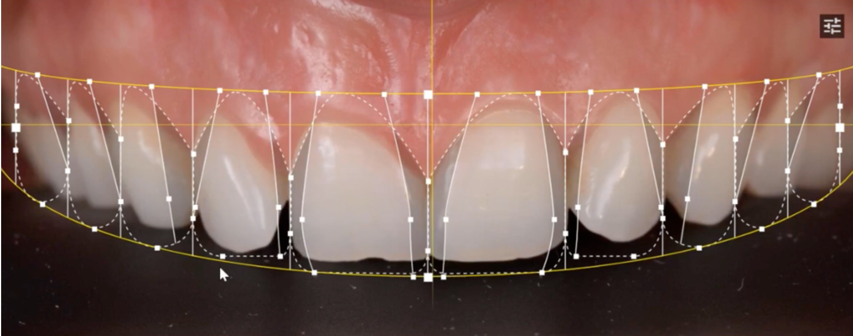

Qu’est ce que la dentisterie restauratrice esthétique ?

La dentisterie esthétique se concentre sur l’amélioration de l’apparence des dents, du sourire et de la mâchoire. Elle diffère de la dentisterie traditionnelle, qui se focalise principalement sur la santé et la fonction dentaire. Les soins esthétiques vous permettent de retrouver un sourire plus harmonieux tout en garantissant le bien-être de vos dents.

Chaque traitement esthétique est adapté à vos besoins spécifiques. L’objectif est d’améliorer l’apparence globale de votre sourire de façon naturelle et durable. Au Cabinet dentaire Claude Monet à Croissy-sur-Seine, une équipe qualifiée vous guide à travers les différentes options de dentisterie esthétique pour obtenir les résultats souhaités.